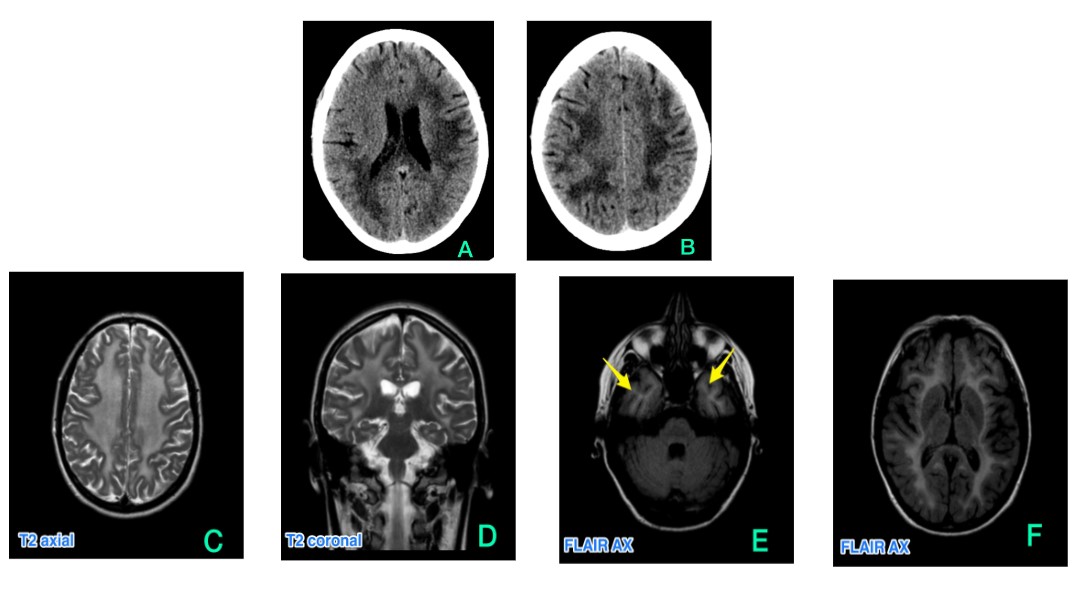

TC de cráneo, cortes axiales (Imágenes A y B). Se observa hipodensidad de la sustancia blanca subcortical de forma generalizada y bilateral. En base a estos hallazgos se pide una RM.

Imágenes de resonancia magnética. Se observa alteración de la intensidad de señal de la sustancia blanca supratentorial y en menor grado en región posterior de la protuberancia y pedúnculo cerebeloso medio derecho (no evidenciado en estas imágenes). La afectación presentaba una distribución extensa, bilateral, y en general simétrica con afectación de todos los lóbulos cerebrales. No mostraba realce tras la inyección de gadolinio IV y respetaba las fibras en U (imágenes C, D, E, F y G)